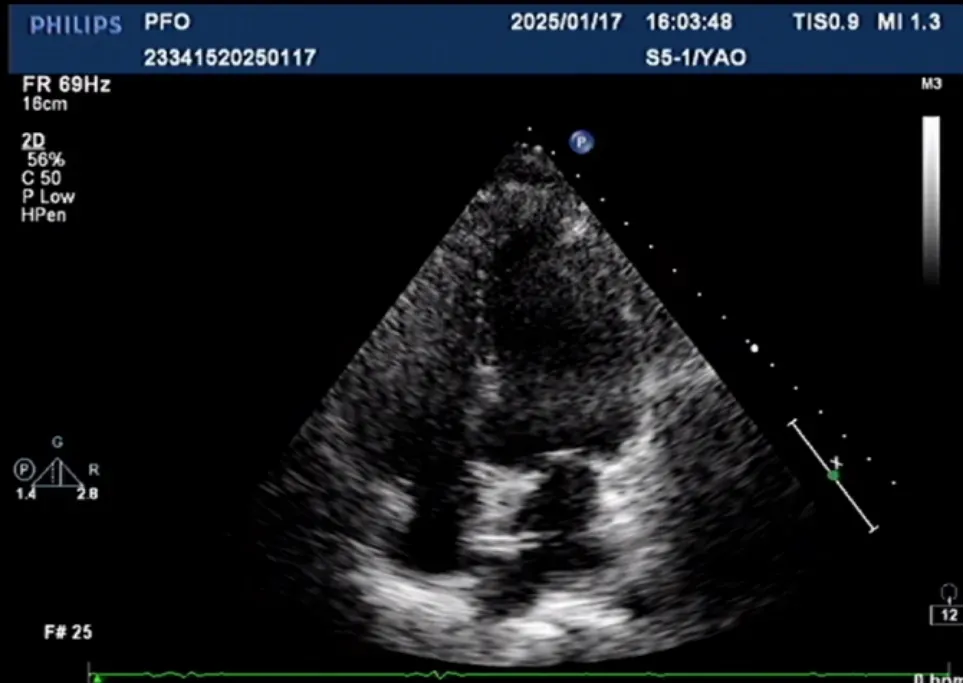

傳送鞘進(jìn)入左房